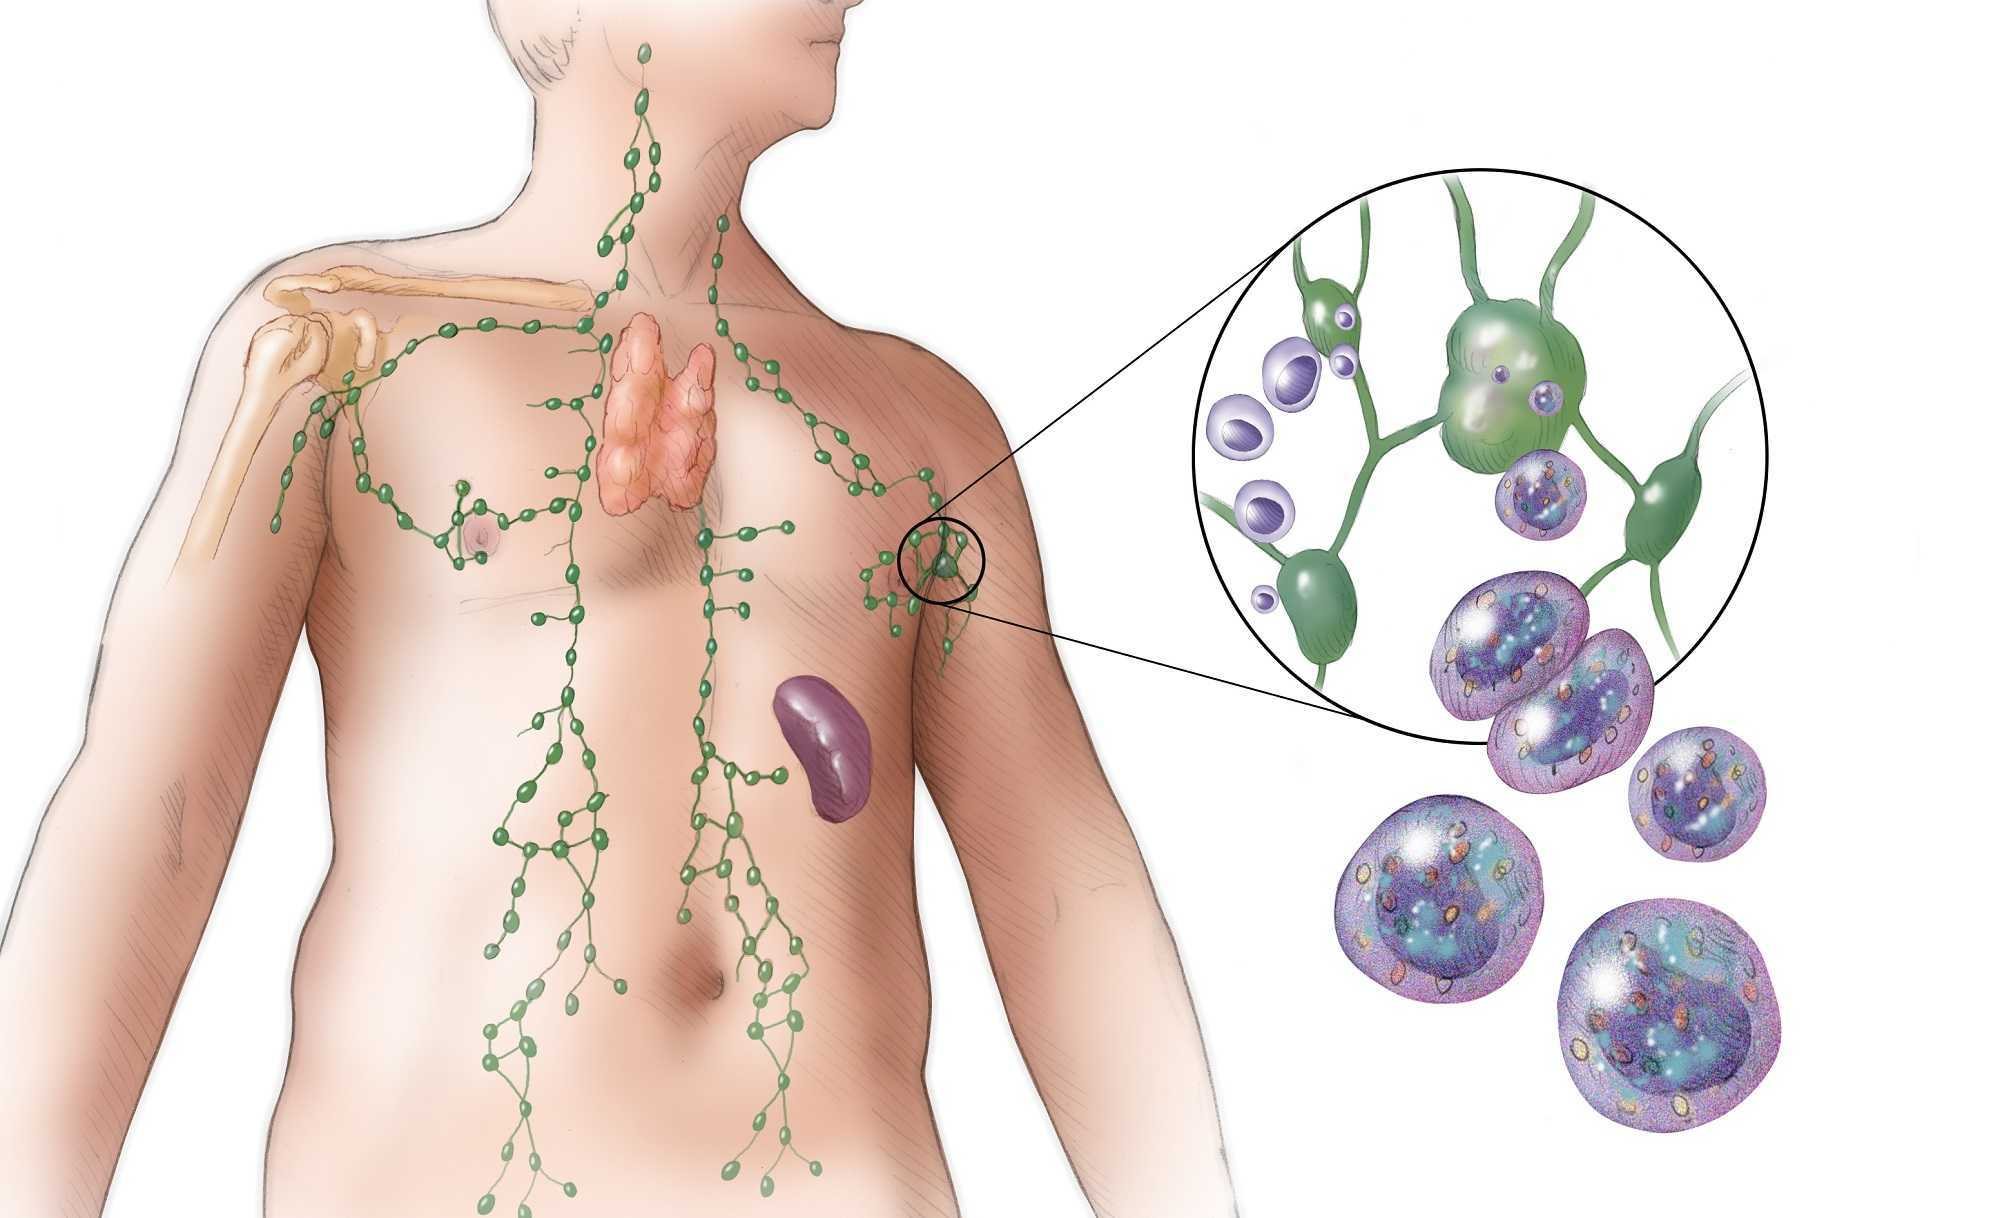

УЗИ лимфоузлов при лимфоме Ходжкина